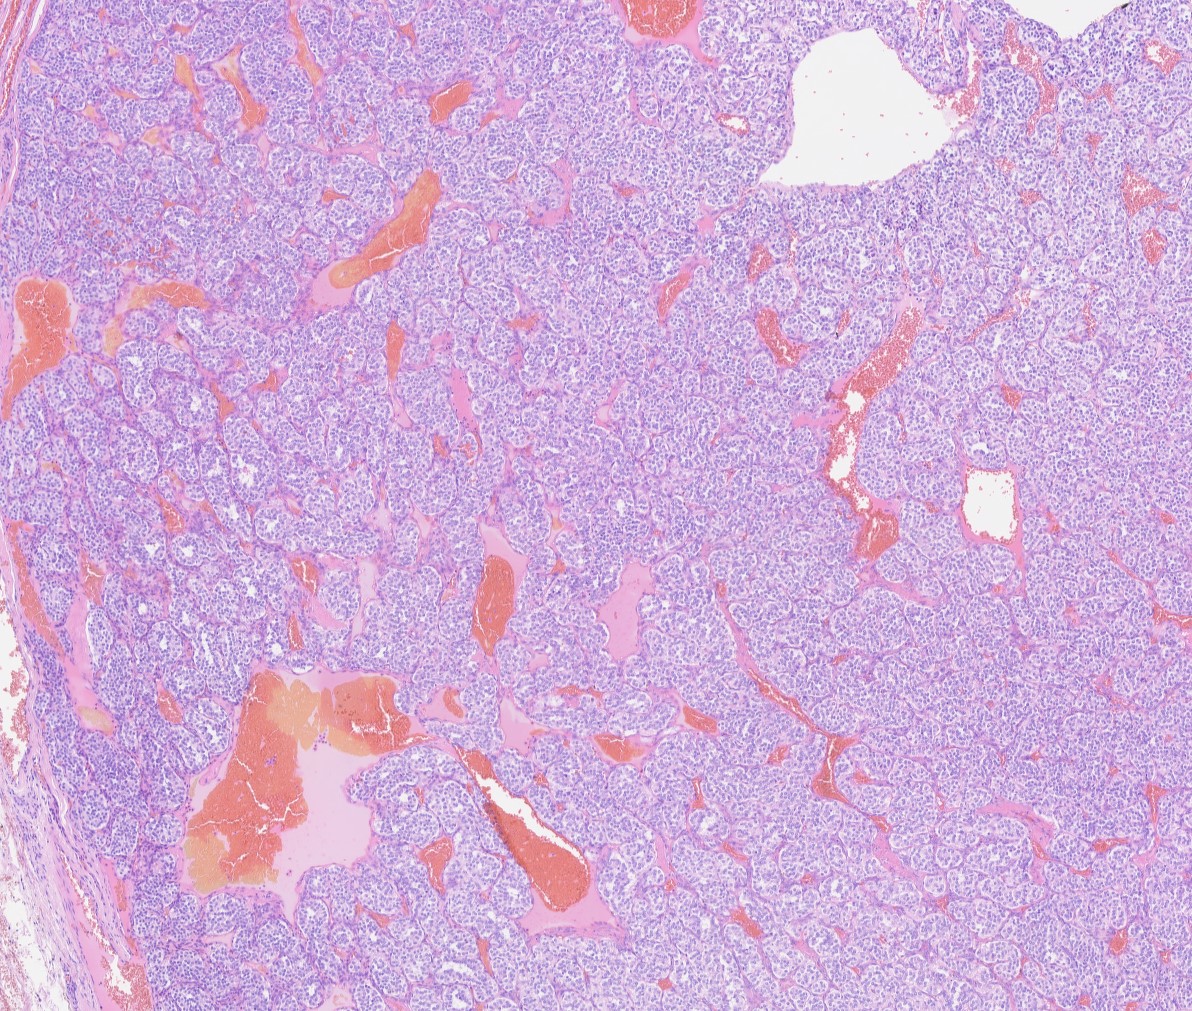

Carotid body paragangliomas are slow growing, well circumscribed tumors with a reddish-brown, firm cut surface. Hemorrhage and cystic degeneration may be seen. On microscopy, nests of oncocytic cells ("zellballen"), often with prominent intranuclear cytoplasmic pseudoinclusions, are surrounded by a fibrovascular network including small spindled sustentacular cells. As demonstrated by this case, an organoid growth pattern is most common in head and neck paragangliomas, but trabecular and solid growth, spindled areas, pigmentation, stromal sclerosis and even amyloid deposition have been described (Head Neck Pathol 2015;9:300). The sustentacular cells stain with S100 and the tumor cells with neuroendocrine markers (synaptophysin, chromogranin, CD56). A reticulin stain will highlight the fibrovascular network. Management is surgical resection (Arch Pathol Lab Med 2014;138:182).

Carotid body paragangliomas are slow growing, well circumscribed tumors with a reddish-brown, firm cut surface. Hemorrhage and cystic degeneration may be seen. On microscopy, nests of oncocytic cells ("zellballen"), often with prominent intranuclear cytoplasmic pseudoinclusions, are surrounded by a fibrovascular network including small spindled sustentacular cells. As demonstrated by this case, an organoid growth pattern is most common in head and neck paragangliomas, but trabecular and solid growth, spindled areas, pigmentation, stromal sclerosis and even amyloid deposition have been described (Head Neck Pathol 2015;9:300). The sustentacular cells stain with S100 and the tumor cells with neuroendocrine markers (synaptophysin, chromogranin, CD56). A reticulin stain will highlight the fibrovascular network. Management is surgical resection (Arch Pathol Lab Med 2014;138:182).